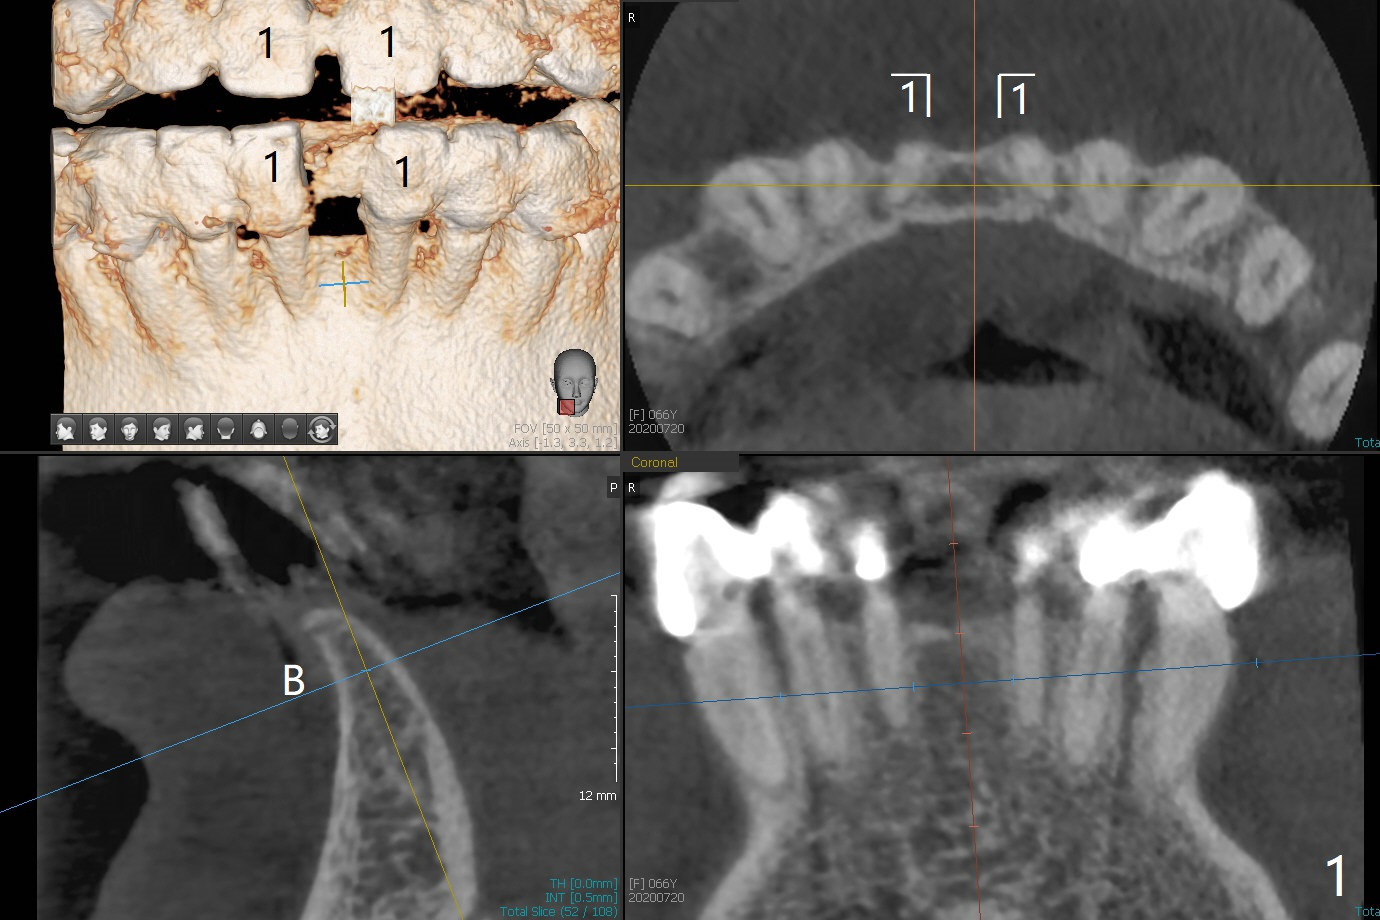

可以重做下颌7个连体牙冠,连接所有牙冠,中缝不再出现,但是费用高,口腔卫生不容易维持。简易办法是种植一个连体植体(1 -piece implant, 2.5x12(4) mm (直径,长度(袖),图二,图三(冠状截面))。 切口暴露狭窄牙槽嵴(图四),截除牙槽顶(图五黑色),然后在平坦骨面开始钻洞(图六红色箭头)。植体尽量种深点防止螺纹暴露,后期骨质密度容易增加。第一个钻头1.5x10毫米,拍摄根尖片,如果方位好,使用2x12mm, 2.5x6 mm钻头,或者2.5mm tap,植体植入。如果方位不好,纠正后,一定要有根尖片证实,才能用下一个钻头。牙槽嵴截除处骨质密度~700单位(图七),不是很高,放置植体前不必用同等大小钻头或者tap。